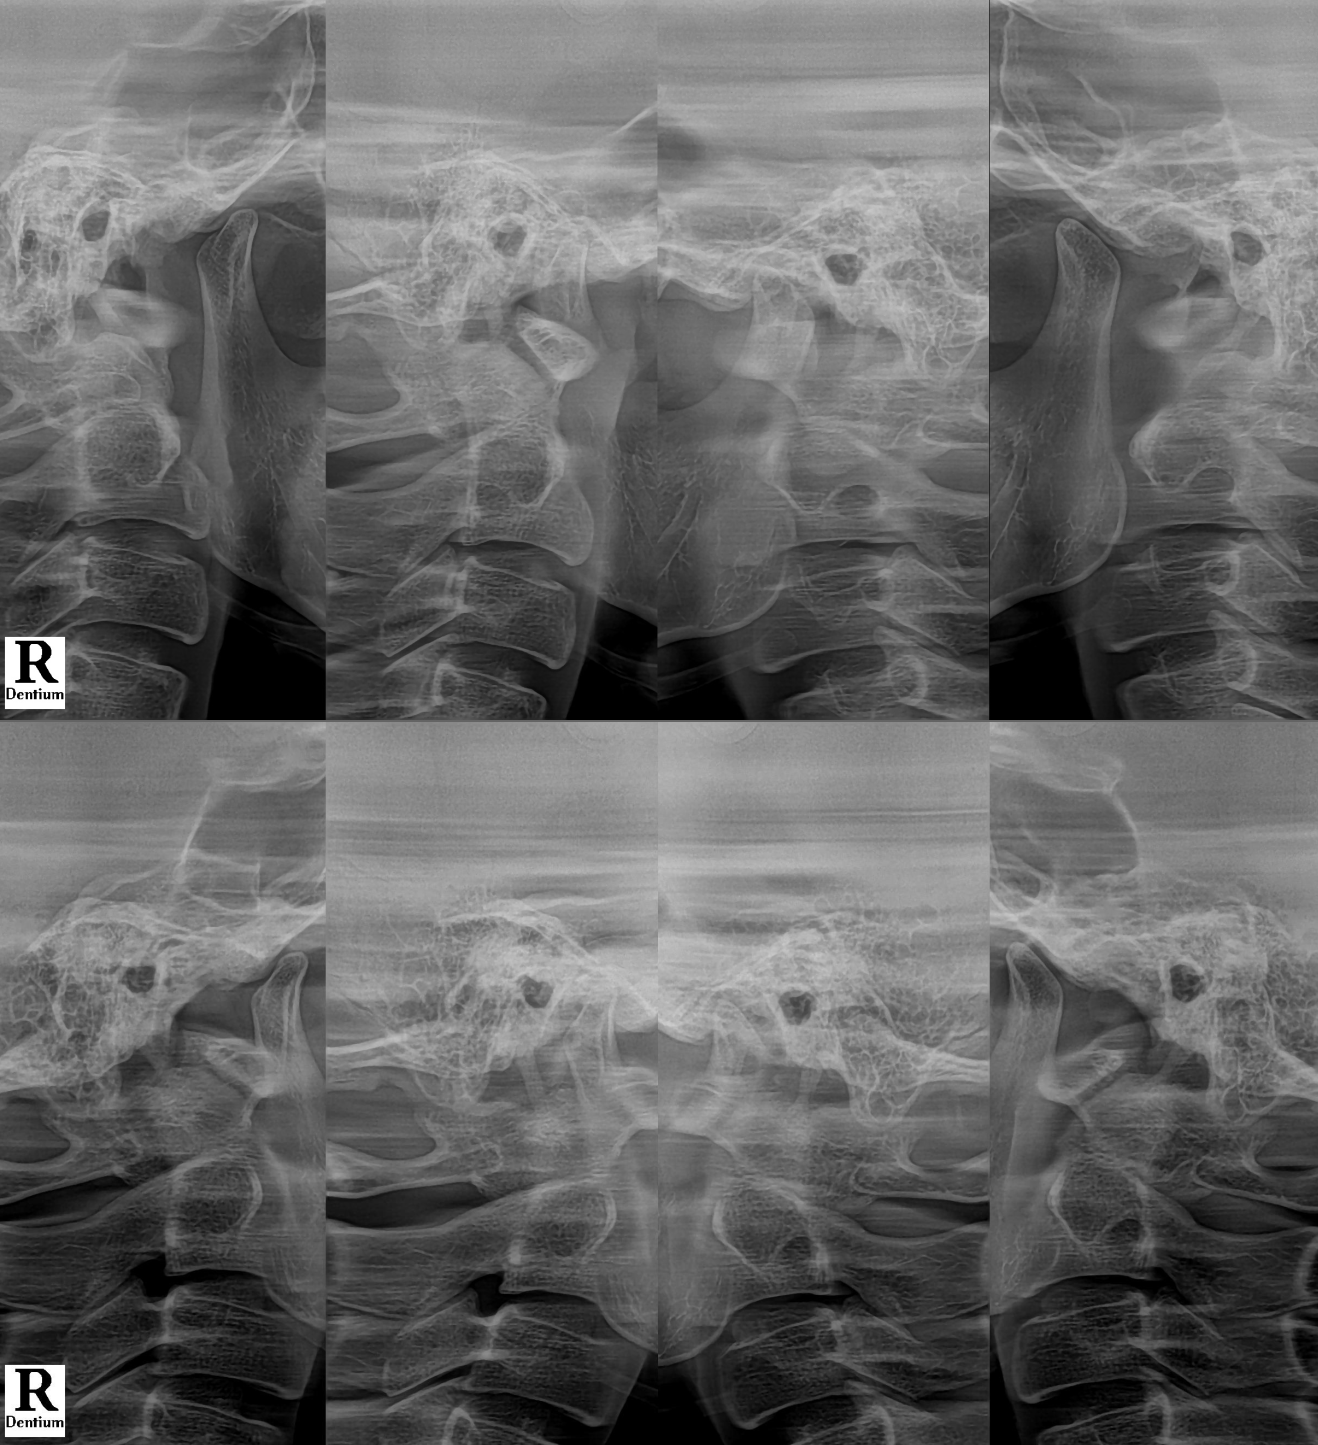

#CaseNo210306

관자놀이 근육, 즉 측두근과

턱관절 주변 근육 긴장이 핵심 원인이었습니다.

👉 턱관절 디스크 불안정

👉 관절 위치 문제

이미 시작되었다는 신호입니다.